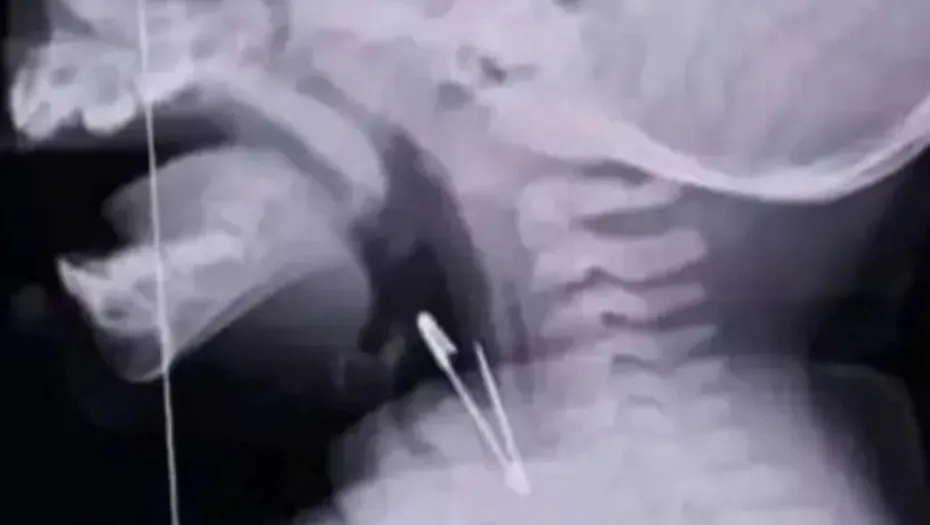

El pasado martes 24 de septiembre, un alumno de tercer grado de la Escuela Mariano Echazú en Tartagal vivió un momento de gran preocupación cuando se tragó un alfiler.

Sus compañeros actuaron rápidamente alertando a las autoridades del colegio, quienes llamaron de inmediato a los servicios de emergencia.

Al llegar, los paramédicos decidieron trasladar al niño al Hospital Juan Domingo Perón. Aunque se contempló la opción de llevarlo a un centro médico más avanzado en Orán, los profesionales optaron por atenderlo en el hospital local.

Una radiografía mostró cómo el objeto punzante se había alojado en la laringe, lo que hizo que la extracción fuera un procedimiento delicado, requiriendo un enfoque minucioso para no comprometer su salud. El padre del pequeño informó que tras una delicada maniobra, los médicos lograron extraer el alfiler de gancho.

Afortunadamente, esta travesura terminó en un gran susto, y aunque el niño permaneció internado por unas horas, ya se encuentra en casa recuperándose bien y siguiendo las recomendaciones médicas para cuidar su garganta.